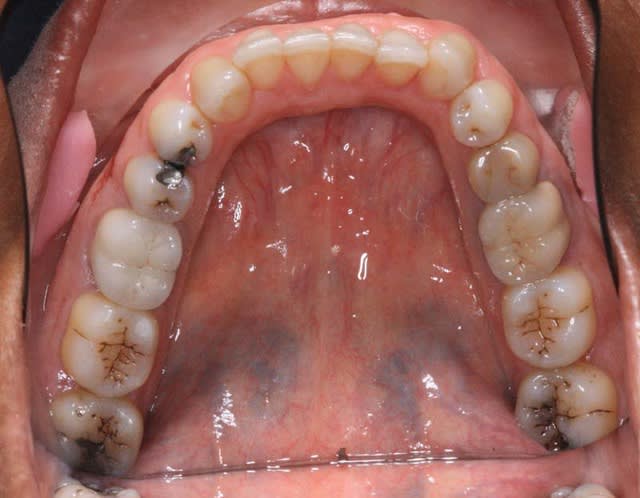

c‘est un cas que j’ai vu ce matin

La patiente (66 ans) se plaint de douleurs au niveau de l’A.T.M.

Pourtant y'a tous les critères de Planas, Md carrée, facettes d'usure, pas de protection canine ( semble-t'il)donc elle devrait pas souffrir, c'est une simulatrice!

P.S.: ce qui est remarquable est qu'il y beaucoup de critères de Planas

Occlusion imparfaite : presque ne bord à bord au niveau incisal

12 : usure ++

perte des protections canines

pas de mylolyse

peu d'usure indiquant un bruxisme horizontal

pas de 8 max sur les photos mais présence de 8 mandibulaires

> interférence des 48/38 avec les 17/27 ?

Au niveau dentodentaire la situation si elle n'est pas idéale n'est pas catastrophique.

baroud69 écrivait: pas de 8 max sur les photos mais présence de 8 mandibulaires

Pas si sûr! on aperçoit les dds sup à la limite du miroir...